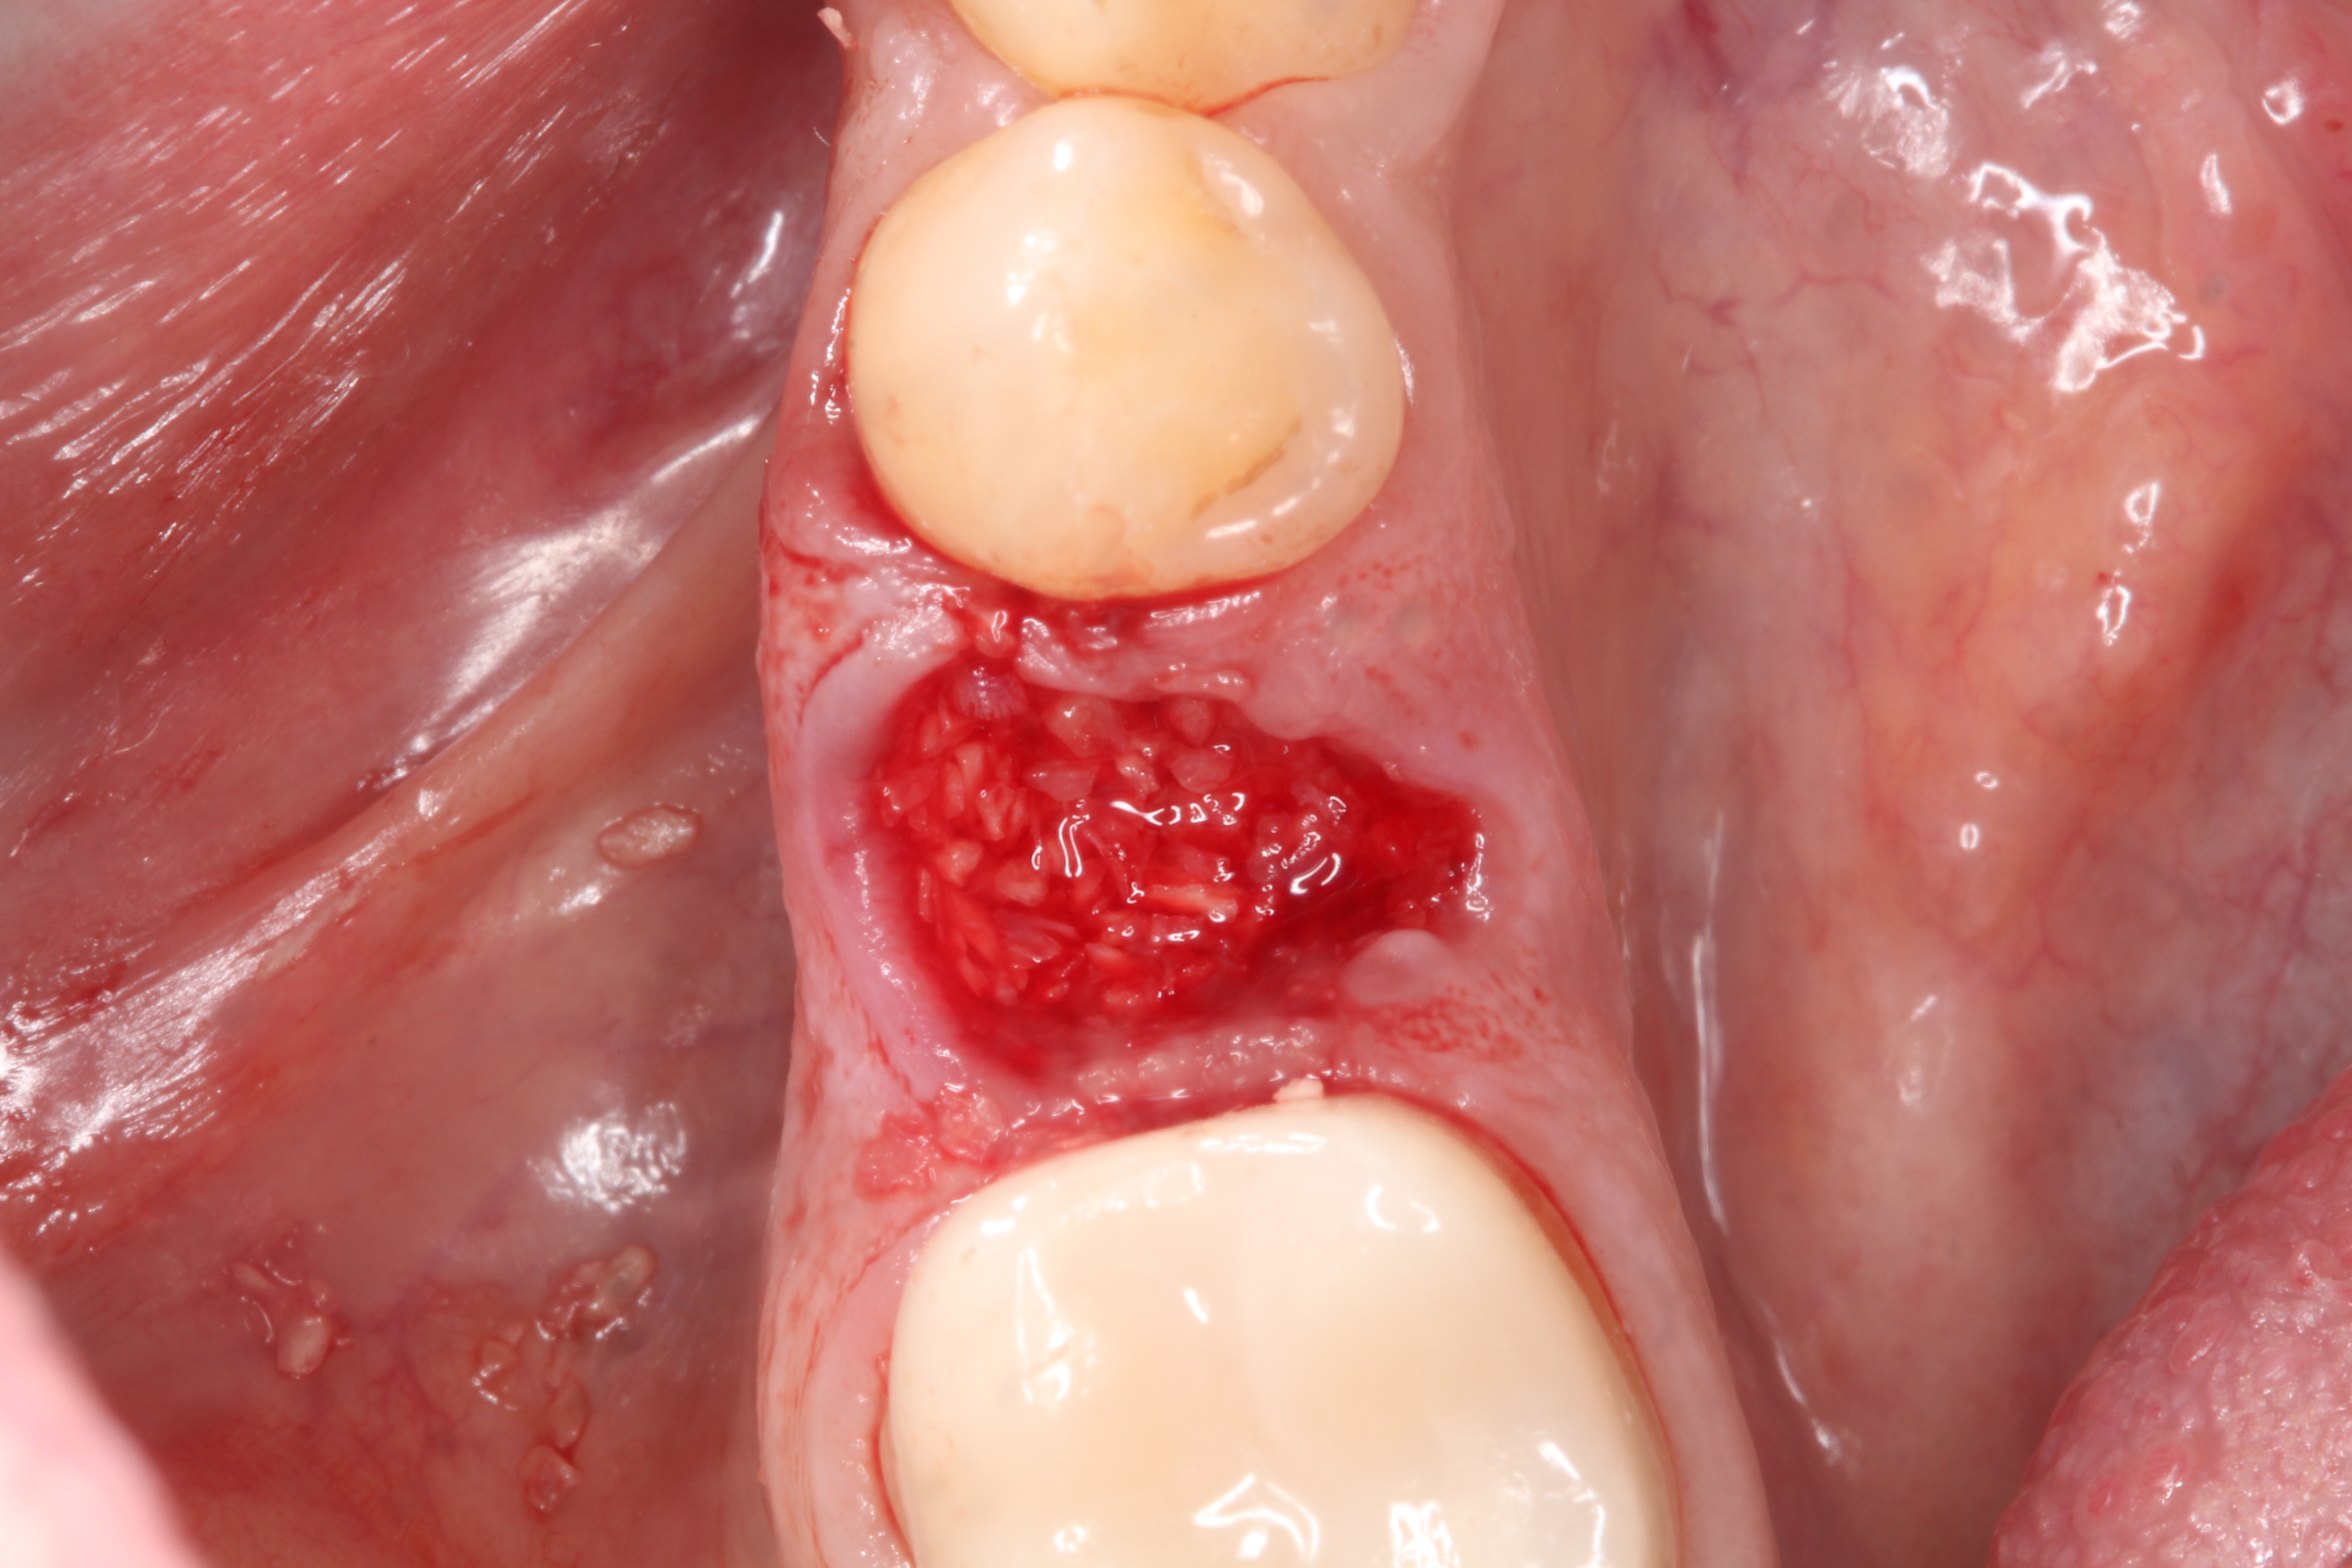

6. Deliver the graft material to the socket, and gently condense the material into the socket. Ensure that the material is evenly distributed into the socket and that no large voids in the graft are present. Do not condense the material or pack it too tightly into the defect. This reduces the space for vascularization and may increase the patient’s postoperative discomfort as well as delay healing of the graft material (Figure 8).

Fig 8. Delivery of the allograft material to the fresh bleeding socket.

Figure 8